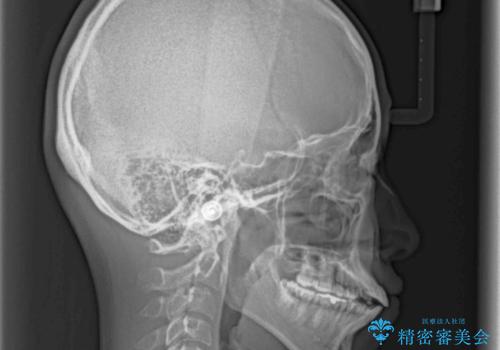

- 上下前歯が前方に飛び出しているとのことで来院された患者様です。

上下左右第一小臼歯4本を抜歯して、積極的に口元を引っ込めるよう、ワイヤー装置にて矯正治療を行うこととしました。

口元の突出感は著しく改善され、横顔の印象が大きく変化しました。